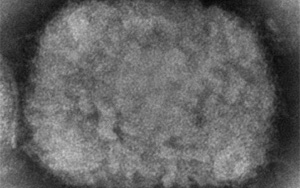

來自波士頓大學喬巴尼安和阿維迪森醫學院的研究人員開發了一種新型化合物,很快就可以用于預防所有經測試的引起人類疾病的痘病毒。